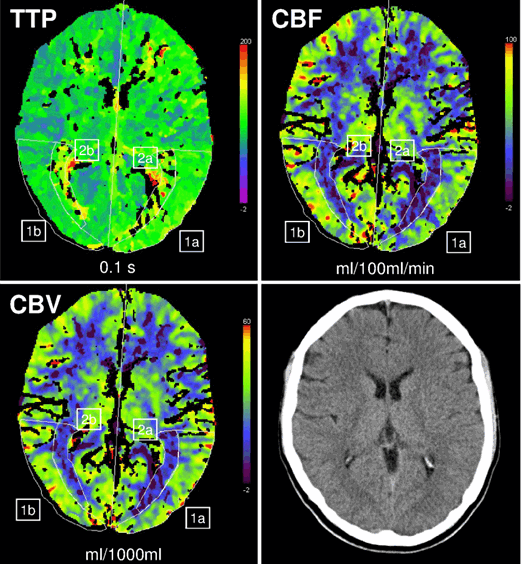

A 24-year-old, right-handed, male student who was living alone, was referred to our emergency ward at 00:30 because of acute speech problems and headache. Exact time of onset could not be determined. The emergency physician reported that the patient called a friend at about midnight indicating speech difficulties. His friend then called an ambulance. He was able to open the door to EMS and walk. Clinical examination demonstrated severe aphasia. In the hospital the patient was unable to speak, read or write, could follow simple commands, was agitated and indicated by gesture that he was having severe headache, photophobia and phonophobia. Suddenly, he started vomiting. No other focal neurological deficits were found. Differential diagnoses included intracranial hemorrhage or ischemic infarction, cerebral venous thrombosis and migraine with aura. Multimodal computed tomography scan was undertaken according to our hyperacute stroke imaging algorithm. Non-contrast computed tomography showed no early signs of cerebral ischemia and ruled out intracranial hemorrhage. Computed tomography angiography (CTA) demonstrated no arterial occlusion or cerebral sinus thrombosis. However, perfusion-CT showed a modest hypoperfusion of the left hemisphere with an area of more severe hypoperfusion in the left Broca and occipitotemporal region which was not restricted to one vascular territory (increase of time to peak (TTP) up to 21%; decrease of cerebral blood flow (CBF) and cerebral blood volume (CBV) up to 38% and 30%, respectively in comparison to the corresponding contralateral area; (Figure 1). Therefore, ischemic infarction was deemed unlikely and consideration of thrombolysis was aborted. At this time the patient’s mother contacted the hospital by phone reporting that her son had called her at 21:30 complaining about blurred vision since 19:00 and a bilateral scotoma wandering from the outside to inside of the visual field for five minutes and paresthesia in his right arm and around the right angle of his mouth. Then a severe pulsating bifrontal headache occurred. At 22:00 during a second telephone call his mother noted he developed progressive problems in finding words. Suddenly, he started vomiting. His mother, father and sister were known to have migraine. He had not been diagnosed as having migraine, but during childhood and adolescence he had about six episodes with visual disorders or numbness in his right arm followed by headaches. However, there had never been vomiting, photophobia or phonophobia.

Figure 1: Perfusion computed tomography shows hypoperfusion of the entire left hemisphere, predominantly in the left Broca’s and occipitotemporal region (time to peak + cerebral blood flow), while cerebral blood volume is above ischemic thresholds (over 60% of average cerebral blood volume in corresponding contralateral unaffected area). Left regions of interest are used for quantification, mirrored regions of interest on the right side. Abbreviations: TTP: time to peak; CBF: cerebral blood flow; CBV: cerebral blood volume; 1: cortical Region of Interest; 2: subcortical Region of Interest, a: hypoperfused tissue; b: normal tissue. Right bottom: non-contrast computed tomography at the level of perfusion CT